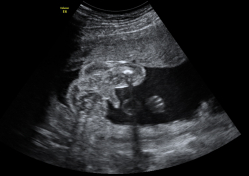

Dilatación de asas intestinales

Dilatación de asas intestinales (*) por obstrucción en feto de 29 semanas. Está anomalía se diagnostica con frecuencia después de la semana 20. Ecografía Embarazo 2D y 3D - SEMANA 20 Ecografía Embarazo 4D - SEMANA 20